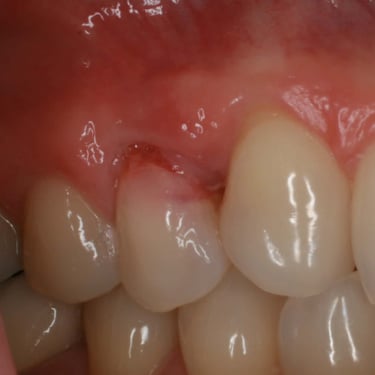

Absceso Periapical Crónico

Un absceso periapical crónico es una infección prolongada en la punta de la raíz del diente que forma una bolsa de pus.

Los pacientes pueden tener dolor leve o no tener síntomas, pero notar una fístula en la encía.

El tratamiento incluye un tratamiento de conducto y, en algunos casos, una cirugía apical. Es crucial tratarlo para evitar la propagación de la infección.